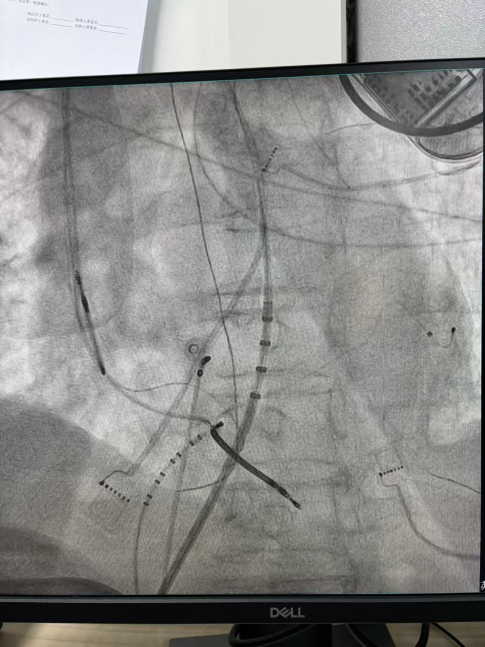

王林林主任医师谨慎操作,成功进入心外膜达到病变位置。术中,患者反复自发多形态室速,且转为室扑,同时出现血流动力学不稳定,需多次电除颤方能终止发作,标测难度极大。这就要求医疗团队必须在有限的标测时间内精准定位室速消融靶点,并结合心内外膜基质特征制定消融策略。经针对性消融后,患者未再自发室速,且室性早搏转为单一形态,经判定为右心室乳头肌来源,随即予以一并消融。术后经心室程序电刺激验证,室速未再被诱发。

右心室后组乳头肌室早电位